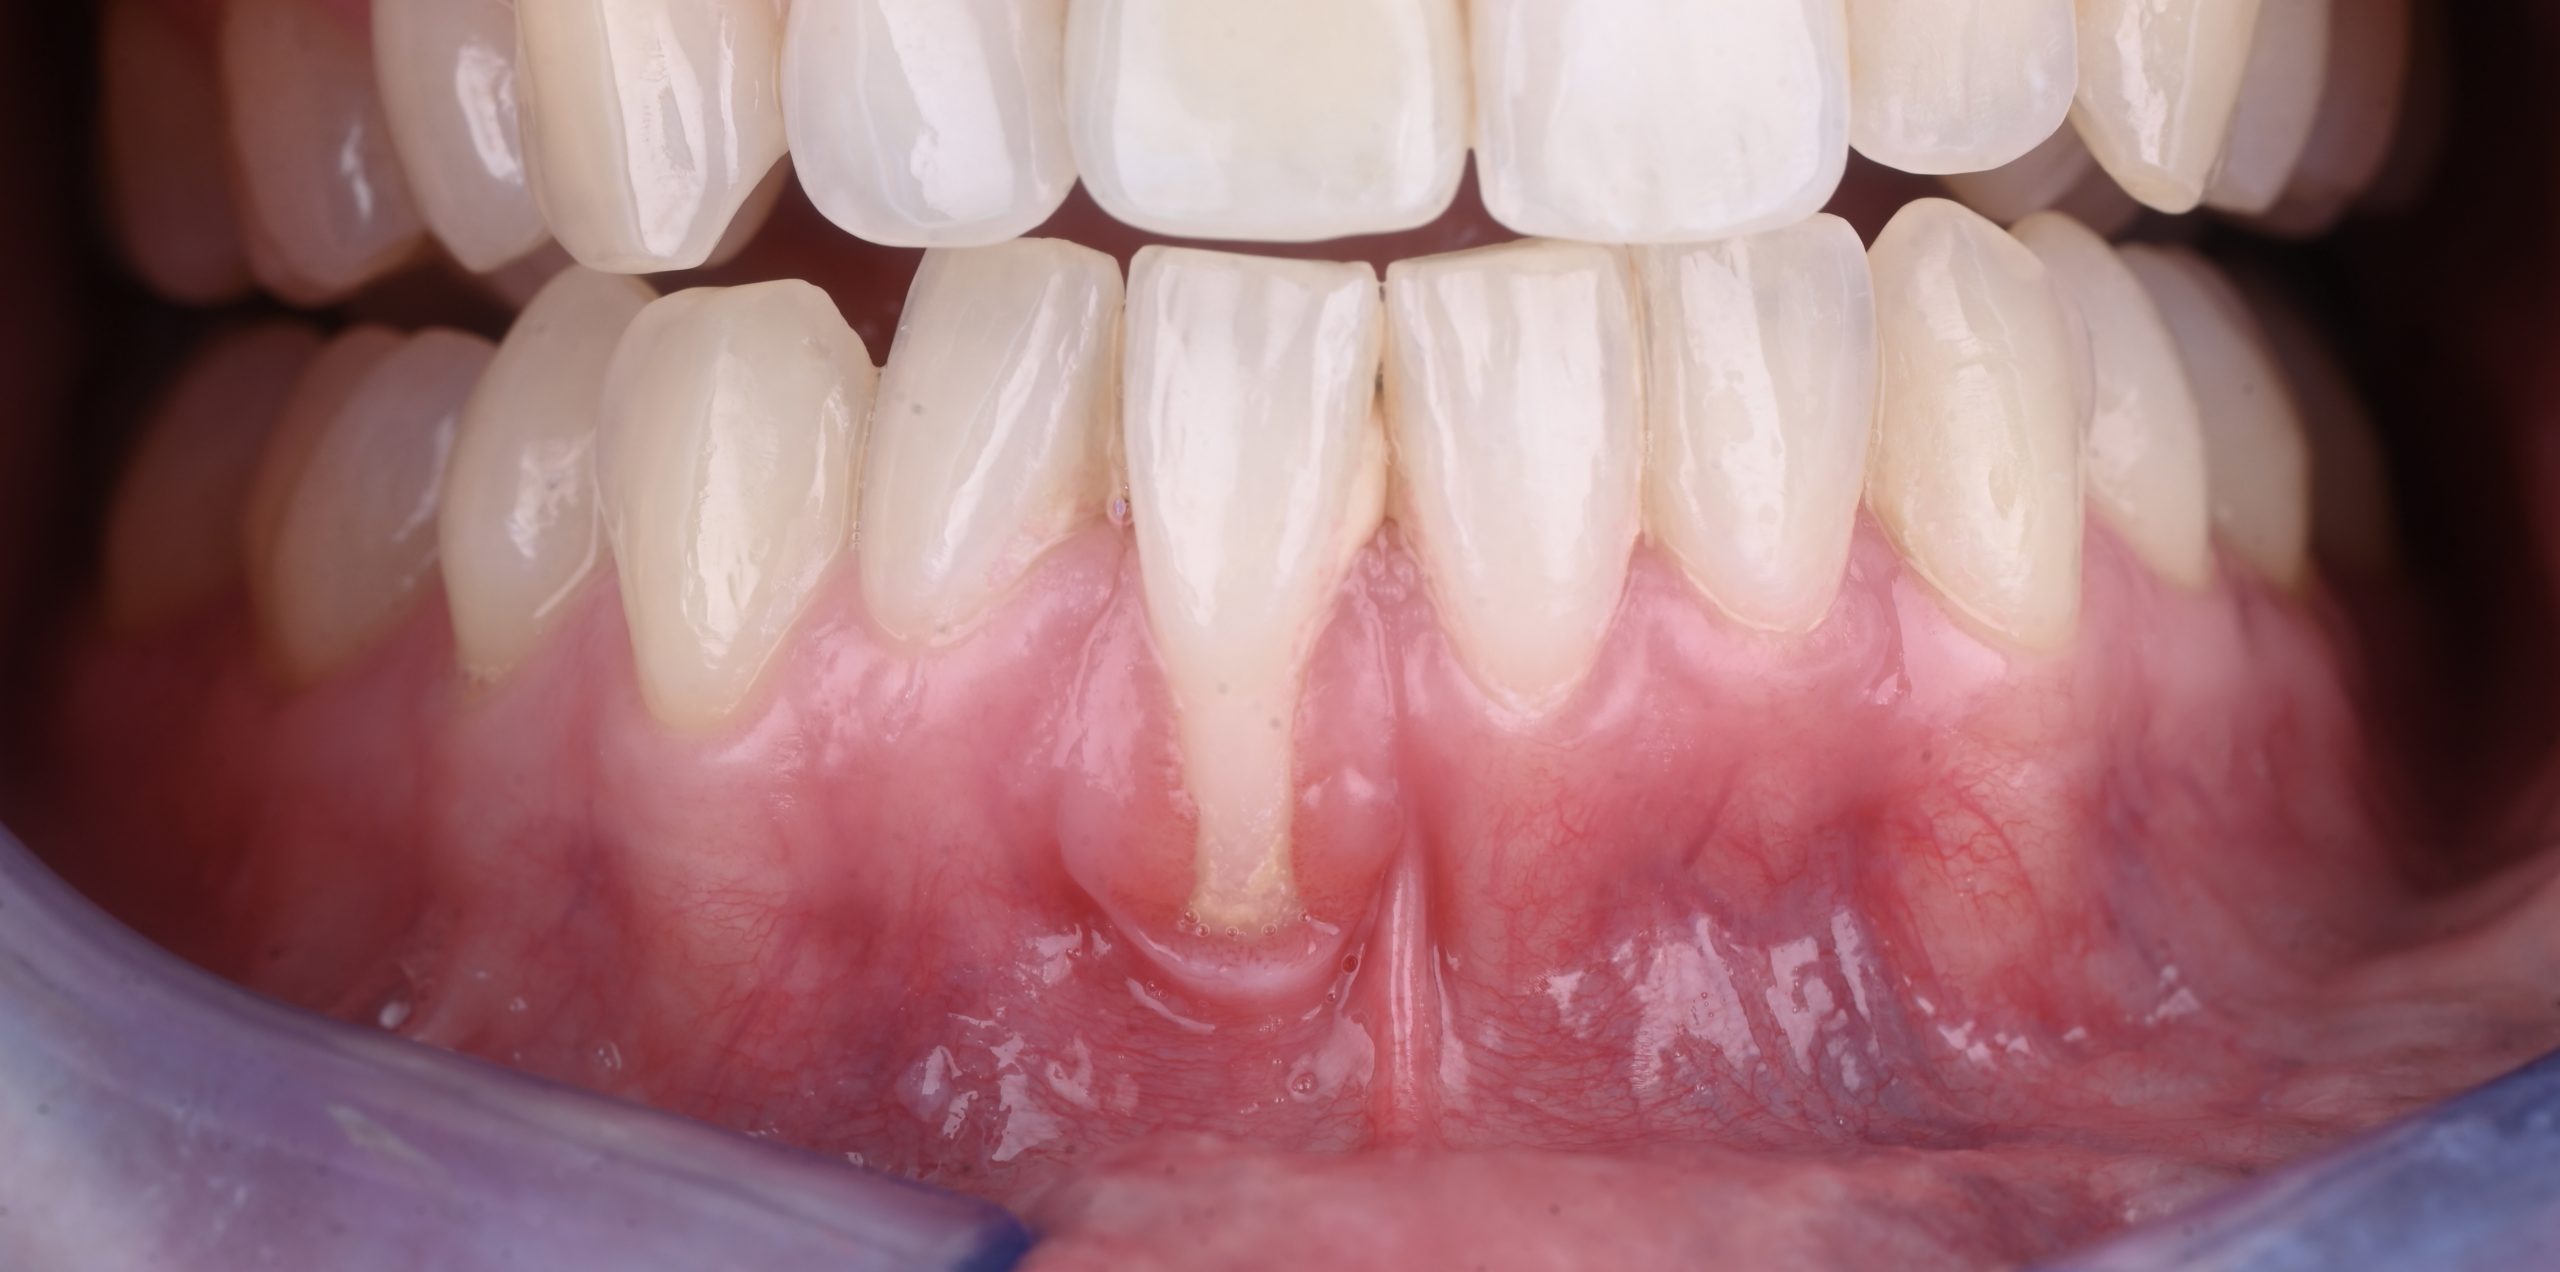

La récession gingivale correspond à un retrait progressif de la gencive qui expose la racine de la dent. Cela peut provoquer :

Une sensibilité accrue au chaud et au froid.

Une gêne esthétique (dents plus longues).

Un risque de caries radiculaires ou de perte d’attache.

Une fragilité osseuse à long terme.